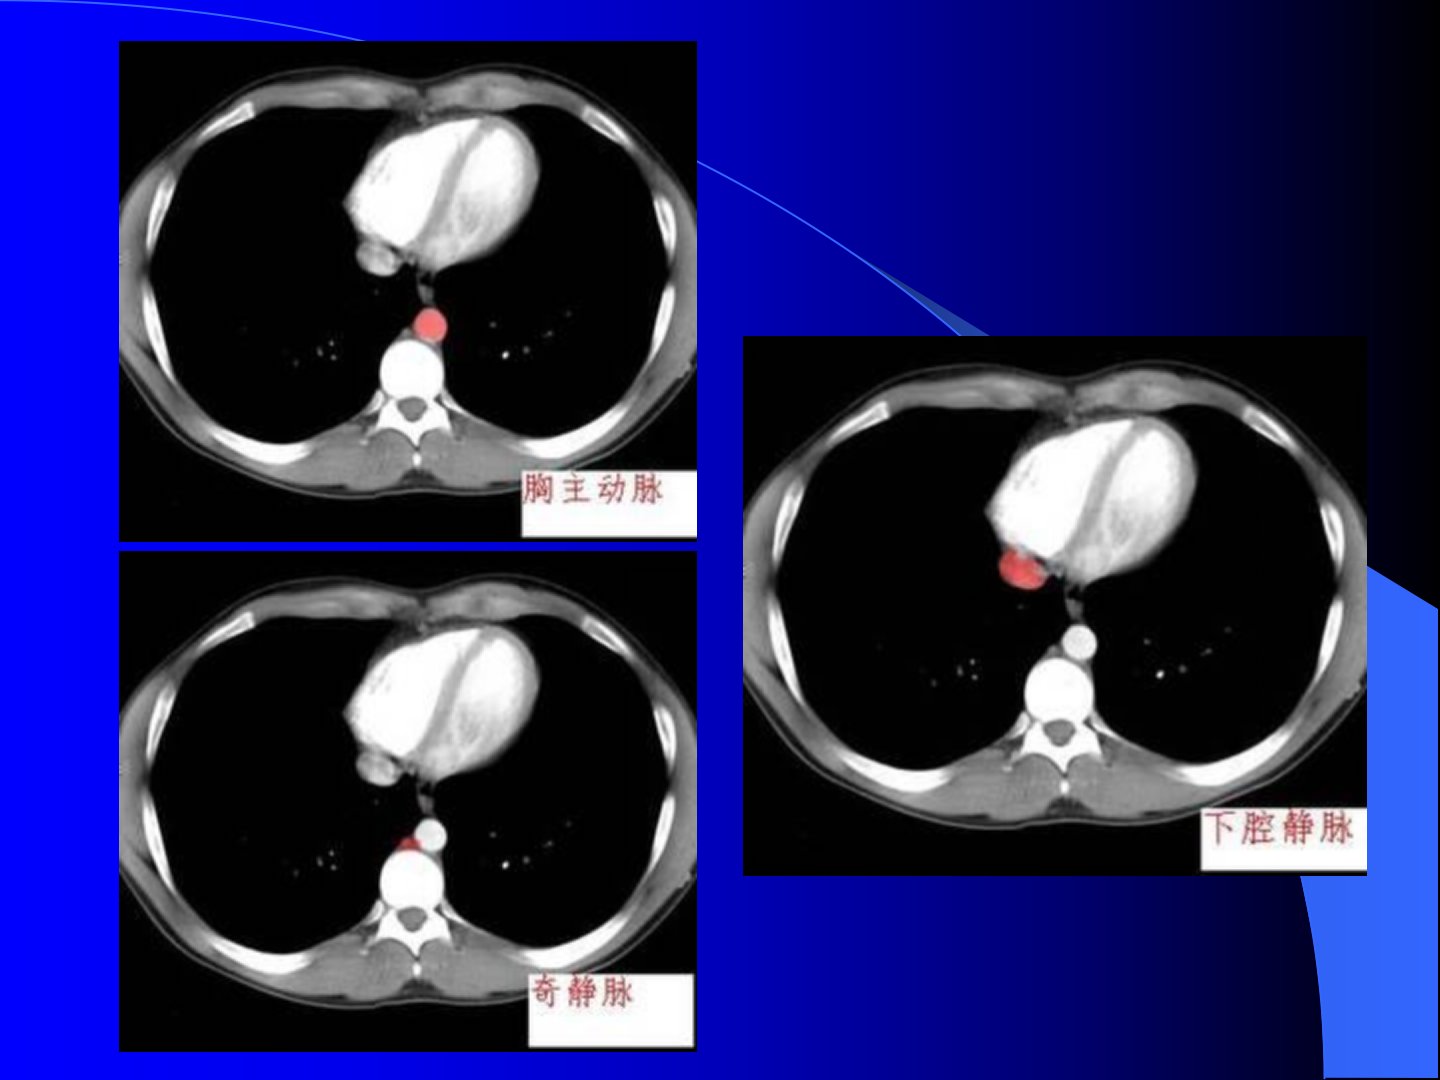

腹部CT诊断腹部CT的检查技术(一) 扫描前准备:扫描前30分钟空腹口服1-2%的泛影葡胺或温开水800-1000ml,下腹部及盆腔应待膀胱充盈后扫描。上检查台前再口服200ml。(二)平扫仰卧位,扫描时宜屏气。(三)增强扫描1、团注非动态扫描;2、团注动态扫描(1)进床式动态扫描(2)同层动态扫描;3、螺旋CT双期或多期增强扫描。(四) 造影CT:肾动脉造影(CTA)、下肢造影CT等肝脏肝脏正常表现1肝实质:密度均匀,CT值40-70hu,高于上腹部其它脏器如脾脏等。2肝血管:包括肝动脉、肝静脉、门静脉,表现为肝内条状、分支状或圆点状低密度影,越近肝门区域和下腔静脉区越粗大。3 肝内胆管:正...